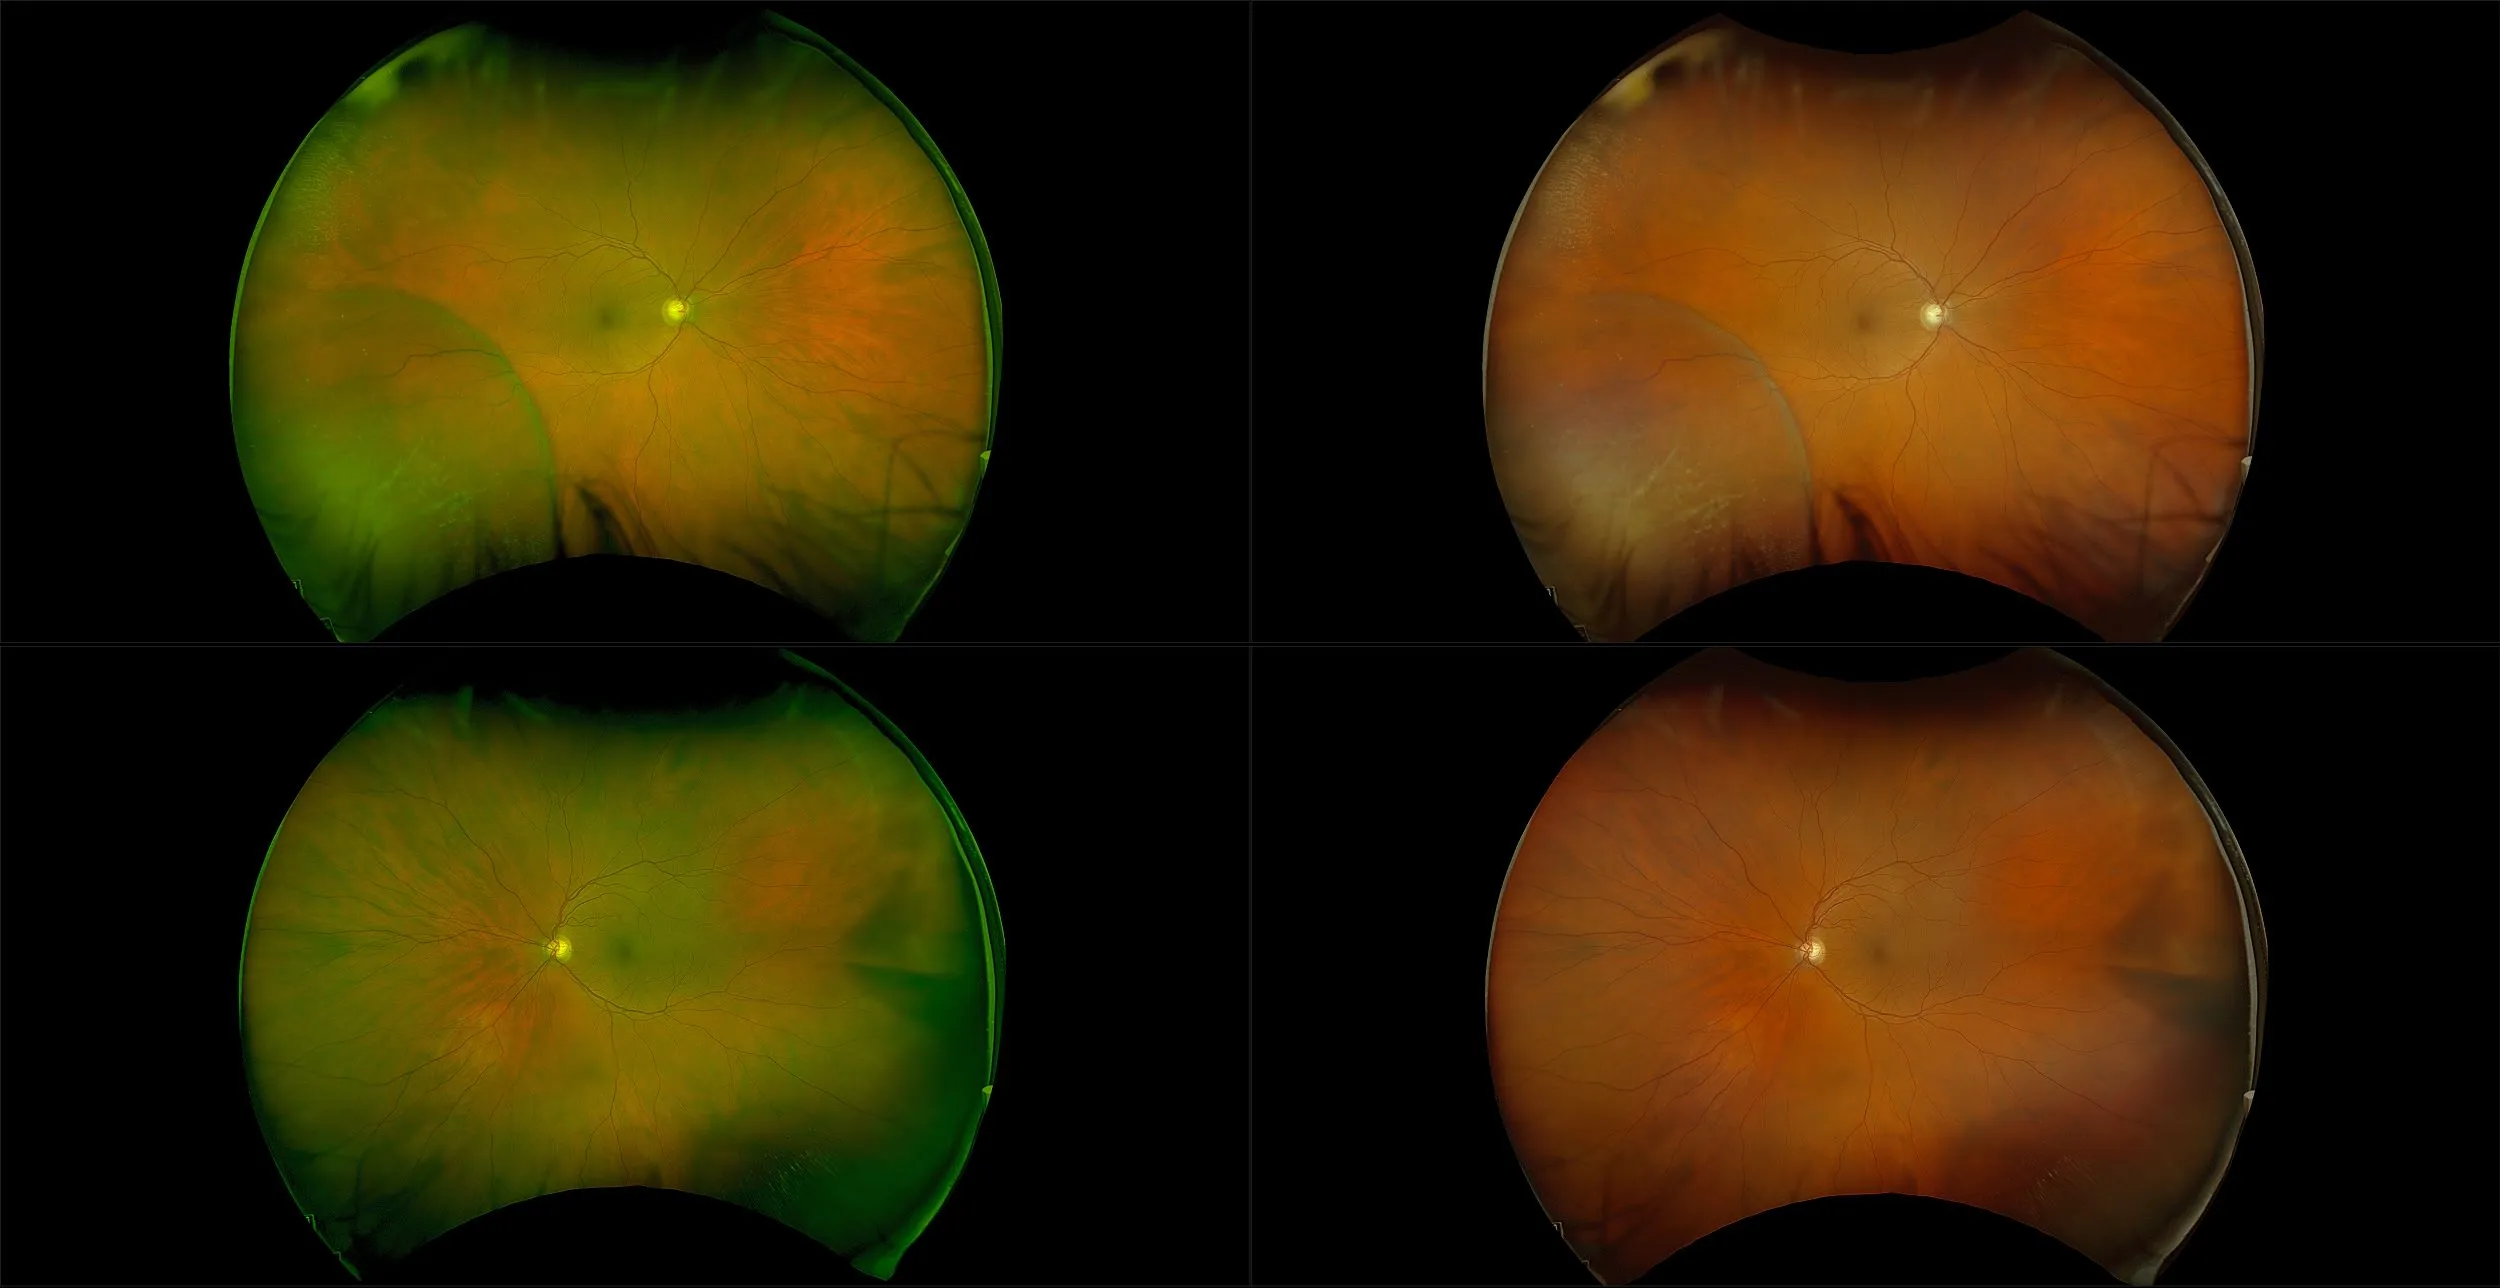

optomap® Recognizing Pathology

This material is designed as a searchable reference resource to support clinical decision-making. The information contained here should be used as general guidance when viewing optomap and OCT images from Optos devices. The differential diagnosis should be made under the direction of the responsible physician. These images were taken on the latest ultra-widefield optomap devices.

The Cases and Images

optomap Recognizing Pathology is searchable by pathology and/or optomap image modality. You may search by multiples of each selection. Each individual case is represented by the accompanying thumbnail image. Most cases include several different optomap image modalities. To view a full description of the case, please click on the thumbnail. Each image in the case will be made available through our OptosAdvance software which provides multi-dimensional visualization of digital images to aid in the analysis of anatomy and pathology. Support and pathology definitions can be found by selecting one of the buttons, above. Should you have questions, please complete the form below.